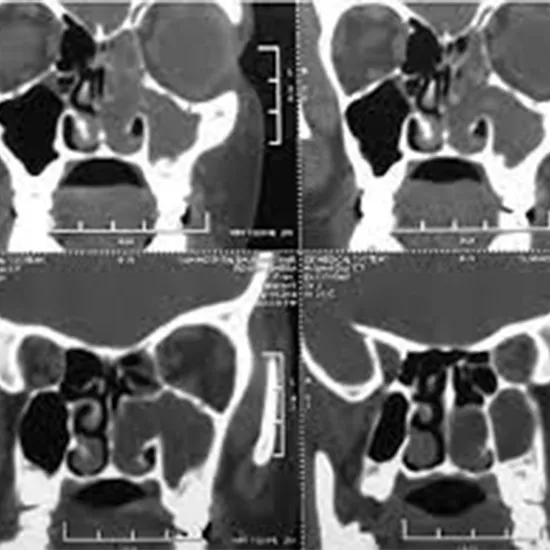

Computed tomography (CT) of the sinuses or nose examines the paranasal sinus cavities, which are hollow, air-filled spaces within the bones of the face surrounding the nasal cavity. CT scanning is non-invasive, painless, and accurate. It is also the most dependable imaging technique for determining whether the sinuses are obstructed, as well as the best imaging modality for sinusitis.

CT of the sinuses is most commonly used to:

• help with sinusitis diagnosis

• Examine sinuses that have fluid in them or thickened sinus membranes.

• detect the presence of infectious diseases

• provide additional information on nasal cavity and sinus tumours

• By defining anatomy, you can plan for surgery.